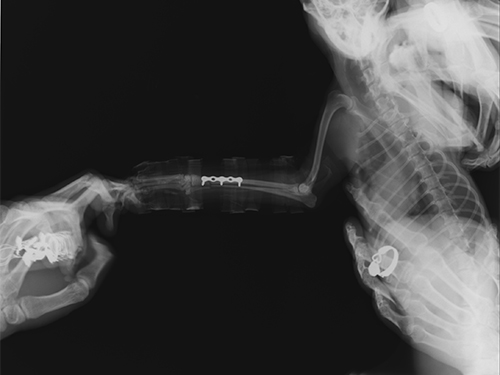

图2:手术前右前肢侧位图

图3:术后正位片